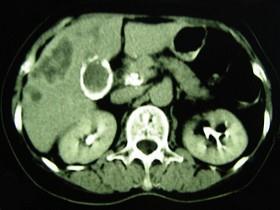

问题 女,66岁,右上腹痛,发热伴有黄疸两月余,消瘦、纳差,影像检查如图,最可能的诊断是()

选项 A.慢性胆囊炎及局灶性脂肪肝 B.胆囊壁钙化及肝血管瘤 C.胆囊癌肝转移 D.肝内胆管细胞癌 E.胆囊癌及原发性肝癌

答案 C